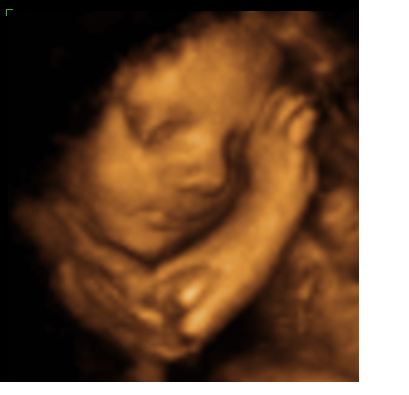

We went for our 4D Ultrasound this weekend and I was so excited to finally get a glimpse at my little one. I am low-risk and my insurance only covers 2 ultrasounds so I haven't seen my little one since 20 weeks (and I'm 30 weeks now). So we loaded up and drove a little ways (as there are not an elective Ultrasound places near us). The whole way down to the place my belly is moving and grooving and turning and as soon as we get there...nothing. He had his hands and feet in front of his face. We did see that we will definitely be having a BOY!!! The tech tried jiggling my belly, filling my bladder, emptying my bladder, I drank ice cold water, juice and ate some candy...he slept through the whole thing. We do get to go back this weekend to try again but I was a little disappointed. Luckily he will be here sooner than later.